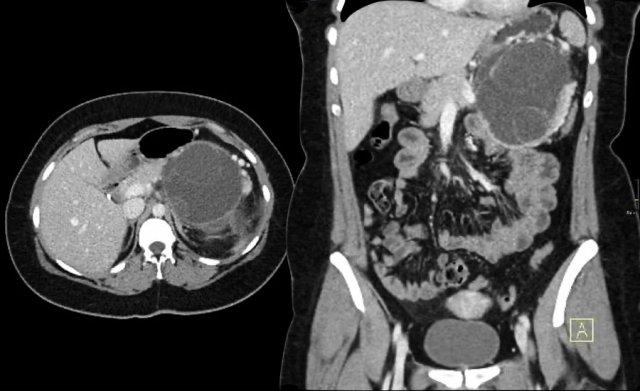

Hình ảnh CT của bệnh nhân nữ 51 tuổi có tiền sử sỏi mật và đau bụng.

Ghi nhận tổn thương giảm tỷ trọng với vôi hóa trung tâm ở đầu tụy.

Tổn thương có bờ viền thùy múi.

Tiếp tục xem hình ảnh MRI.

MRI thể hiện rõ hơn các đặc điểm hình thái của tổn thương (hình).

Trên chuỗi xung T2W, tổn thương có dạng đa nang.

Lưu ý vùng giảm tín hiệu trung tâm do sẹo trung tâm kèm vôi hóa.

Mặc dù một số nang có kích thước khá lớn, đây vẫn là hình ảnh đặc trưng của u nang tuyến thanh dịch (dạng đại nang).

Một ví dụ khác về u nang tuyến thanh dịch (Hình).

Hình ảnh sau tiêm thuốc cản quang bên phải cho thấy tổn thương giảm tỷ trọng với vôi hóa trung tâm ở thân tụy và ngấm thuốc nhẹ của các vách ngăn.

Lưu ý rằng trên CT rất khó nhận ra bản chất dạng nang của các tổn thương này và có thể nhầm lẫn với ung thư biểu mô tuyến tụy.

MRI sẽ dễ dàng thể hiện bản chất dạng nang của các tổn thương này (hình).

Chuỗi xung T2W với xóa mỡ (fatsat) thể hiện rõ tổn thương tăng tín hiệu dạng thùy múi với sẹo trung tâm, đây là hình ảnh đặc trưng của SCN.